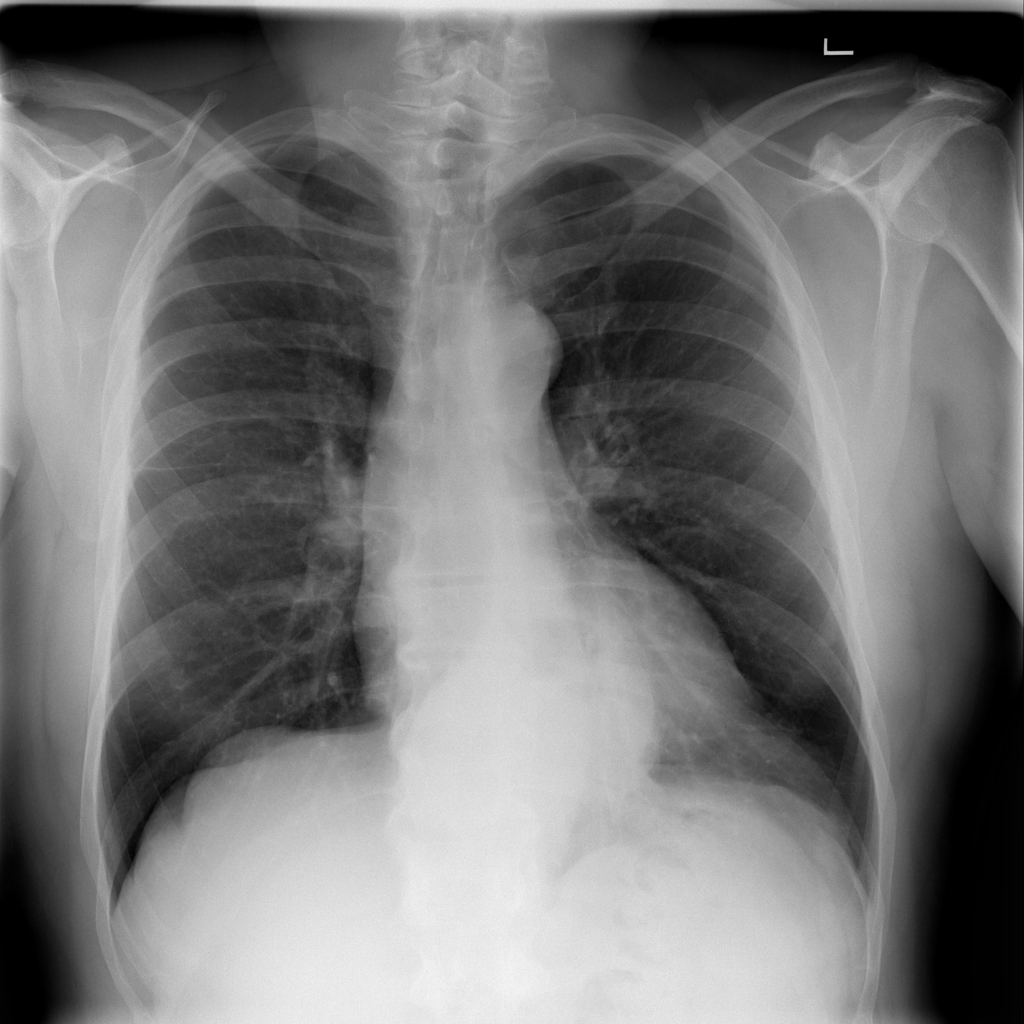

Cardiomegaly

Cardiomegaly means the heart appears enlarged on the chest X-ray. It is a descriptive imaging finding that can be related to heart strain, chronic pressure or volume changes, or even projection effects.